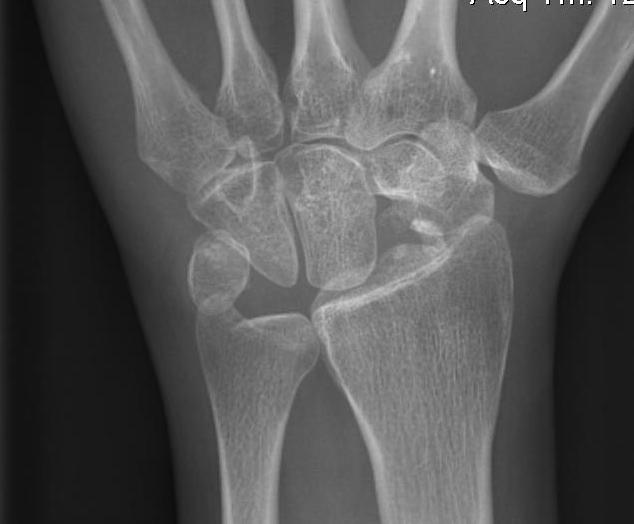

Definition

Scaphoid non union advanced collapse

Diagnosis

Xray / CT

- non union of scaphoid

- radio-scaphoid OA